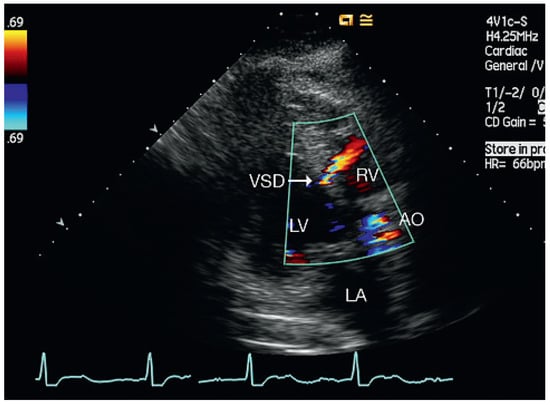

Muscular Ventricular Septal Defect After Mitral and Aortic Valve Replacement